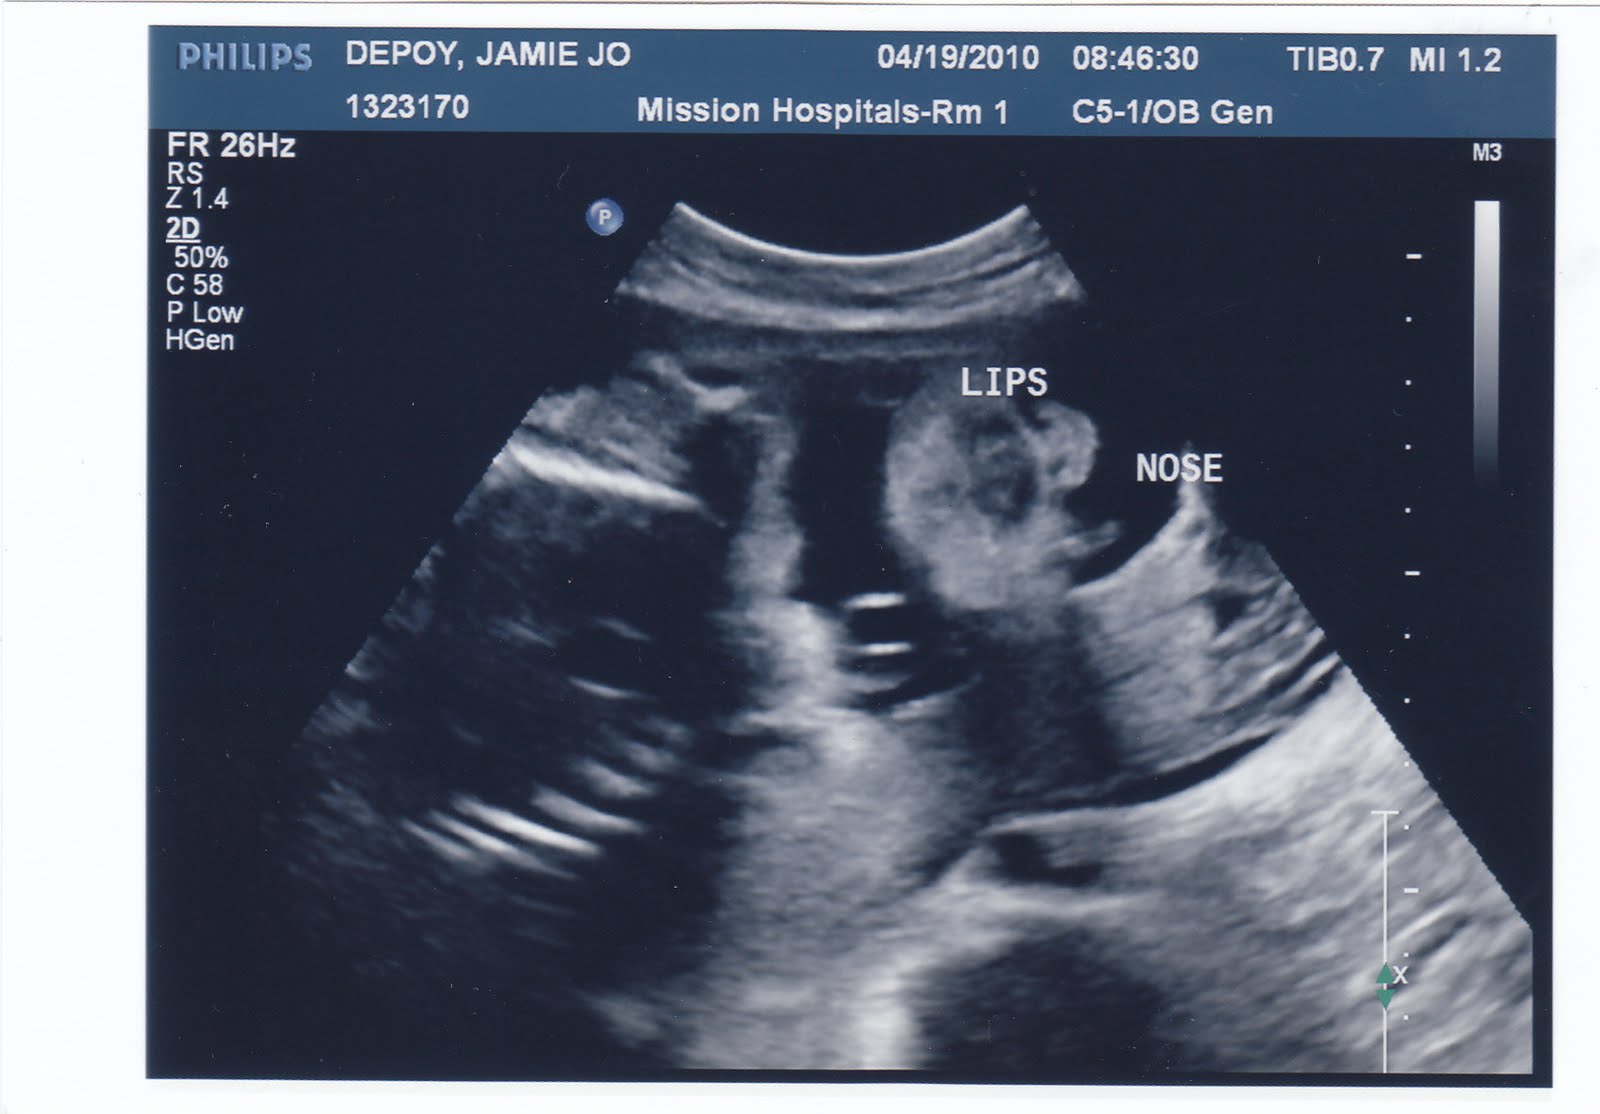

From jamiedepoy.blogspot.com

Sticks and Stones Ultrasound Pics Long Nose On Ultrasound The nasal bone is best assessed in the second trimester, and its measurement is a standard component of a routine 2 nd. the bone present in the nose of your baby should already be developed between 11 and 14 weeks’ gestation and be visible at the. this short letter describes the technique and normal anatomy of the nasal.. Long Nose On Ultrasound.